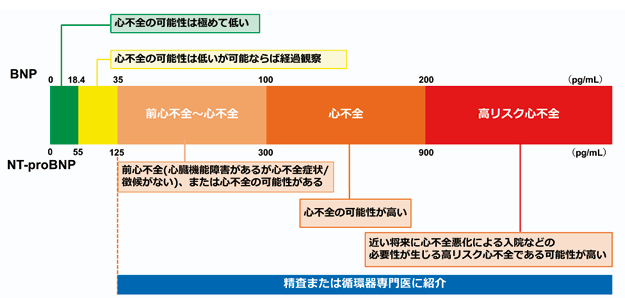

心不全とは?

心不全とは「心臓が悪いために、息切れやむくみがおこり、だんだん悪くなり、生命を縮める病気」と定義されています。ナトリウム利尿ペプチド(BNP/NT-pro BNP)の上昇(図1)と心臓由来の肺うっ血または体うっ血の客観的所見によって裏付けられています。

BNP 100pg/ml、NT-pro BNP 300 pg/mlが

心不全増悪のcut off

<図1 BNP/NT-pro BNPを用いた心不全診断や循環器専門医への紹介基準のカットオフ値>

出典:日本循環器学会 2025年改訂版心不全診療ガイドライン

BNP 100pg/ml、NT-pro BNP 300 pg/mlが心不全入院・増悪のcut off値でありますので、血液検査で上昇しておられる患者様、左室肥大に対する精査が必要な患者様がおられましたらいつでもご紹介ください。